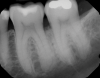

Fig 4. Periapical radiograph revealing a distal intrabony defect at tooth No. 19.

Figure 4

Fig 14. Periapical radiograph revealing healed bone at 1-year follow-up.

Figure 14

In the present case, the patient's postoperative protocol included the administration of analgesics and mouthrinse. Plaque control and polishing were performed every 2 to 3 weeks for the first 3 months. The patient was then placed on a 3-month recall system. At the 1-year follow-up, stability of the soft and hard tissues could be observed (Figure 13 and Figure 14). Following the seven-key checklist, this clinical case demonstrated that correct case selection, with consideration given to patient-, tooth-, defect-, and operator-related factors, combined with the use of an evidence-based surgical protocol, led to predictable outcomes.